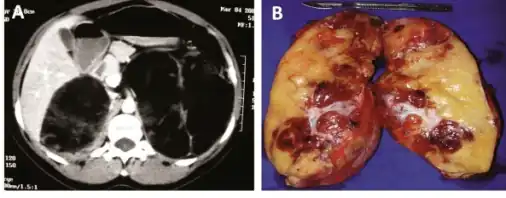

a)CT scan showing heterogeneous bilateral myelolipomas b) macroscopic aspect of left adrenal myelolipomas

Myelolipomas are usually found to occur alone in one adrenal gland, but not both. They can vary widely in size, from as small as a few millimetres to as large as 34 centimeters in diameter. The cut surface has colours varying from yellow to red to mahogany brown, depending on the distribution of fat, blood, and blood-forming cells. The cut surface of larger myelolipomas may contain haemorrhage or infarction.[1]

The cut surface shows colour variegation from yellow to red to brown depending on the distribution of fat, blood and myeloid elements